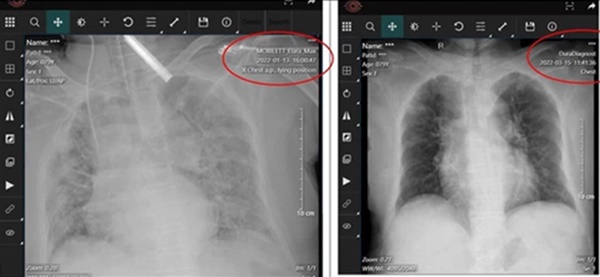

Ngay tại BV Hồi sức Covid-19, BS Hải cho biết có bệnh nhân 80 tuổi, không tiêm vắc xin Covid-19, bệnh nhân lại bị tăng huyết áp. Khi bệnh nhân vào viện đã được đặt ống nội khí quản ở một bệnh viện thành phố và tiên lượng tử vong chắc chắn, với 2 lá phổi trắng xoá. Bệnh nhân được chuyển đến Bệnh viện điều trị người bệnh Covid -19 Hoàng Mai trong một hy vọng mong manh.

Bệnh nhân được thở máy, được dùng thuốc chống virus đường tiêm, corticoid, chống đông, kháng sinh điều trị bội nhiễm, và các biện pháp hồi sức tích cực khác. Bệnh nhân đã được thử rút ống 2 lần thất bại, bác sĩ đã phải cố gắng đến lần 3 thì thành công.

Sau 2 tuần ở bệnh viện dành cho người bệnh Covid-19 khi đã âm tính, bệnh nhân chuyển về Bệnh viện ĐH Y Hà Nội và tiếp tục được điều trị 2 tuần tại Bệnh viện Đại Học Y Hà Nội rồi ra viện trong tình trạng không phải thở oxy.

Sau 1 tháng khi ra viện, ngày 15/3 bệnh nhân khám lại tức 2 tháng kể từ thời điểm nhiễm vẫn chưa đủ thời gian theo định nghĩa để coi là hậu Covid-19, thì phổi của bệnh nhân đã sáng lên rất nhiều, bệnh nhân đang phục hồi dần.